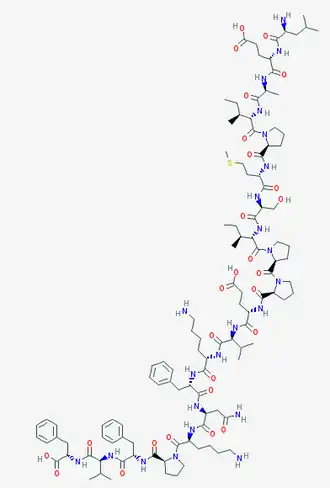

The VIR-576 is a peptide.[7] Consequently, it is a molecule formed by a sequence of amino-acids united by peptide bonds. If we compare both primary structures, it can be seen that the VIR-576 has 2 subunits. Each subunit, monomer is a variant form, a mutant of the VIRIP,[1] differing from four amino acids.

Thus, among the new ones introduced, it is important to emphasize the importance of the cysteine (C) introduced replacing the methionine (M), both being sulfated amino acids, in the stabilization of its structure.

VIR-576 can establish more hydrogen bonds because it has 41 H-bond donors and 56 H-bond acceptors[8] in comparison with the 23 H-bond donors and 30 H-bond acceptors[9] of the VIRIP.Therefore, it's able to form more interactions and react with the gp-41 in a higher intensity than the VIRIP.

Another important interaction that we must underline is the disulfide bond established between both cysteines of the two monomers of the VIR-576 which allows the peptide to have more structural stability in the space in comparison with the VIRIP. Moreover, the ring form that appears in the secondary structure is due to this interaction between both sulfate atoms. Thanks to this disulfide bond, a cystine is formed. This fact allows the union of the subunits during the reaction with the gp41 and also allows them to act simultaneously. Thanks to all this activity and to the dimerization respect to the VIRIP, the VIR-576 is more effective.[10]